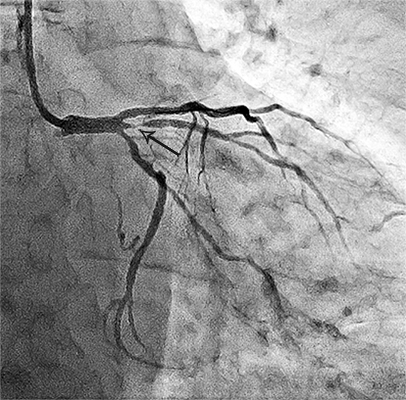

Приклади коронарограм:

стеноз правої коронарної артерії    стеноз лівої коронарної артерії

Звуження (стеноз)

правої коронарної артерії

Звуження (стеноз) гілки

лівої коронарної артерії.